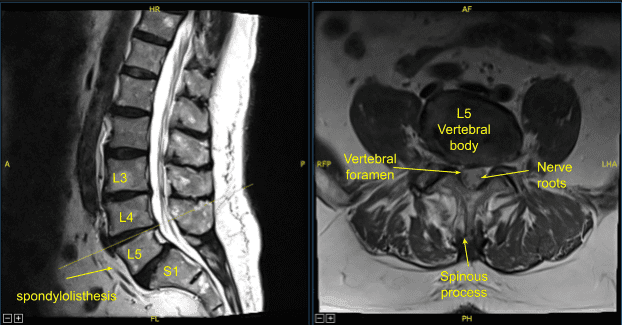

A patient presented to our clinic with signs and symptoms of lumbar spondylolysis, spondylolisthesis and spondylotic radiculopathy. Having failed conservative treatment measures, surgery was offered and recommended to decompress and stabilize the lumbar spine.

The patient was followed up two weeks after their surgery and then continued to follow up in our office 4, 6, and 8 weeks after the surgery. The patient showed gradual signs of improvement with lumbar spondylolysis, spondylolisthesis and spondylotic radiculopathy.

Sagittal View Axial View